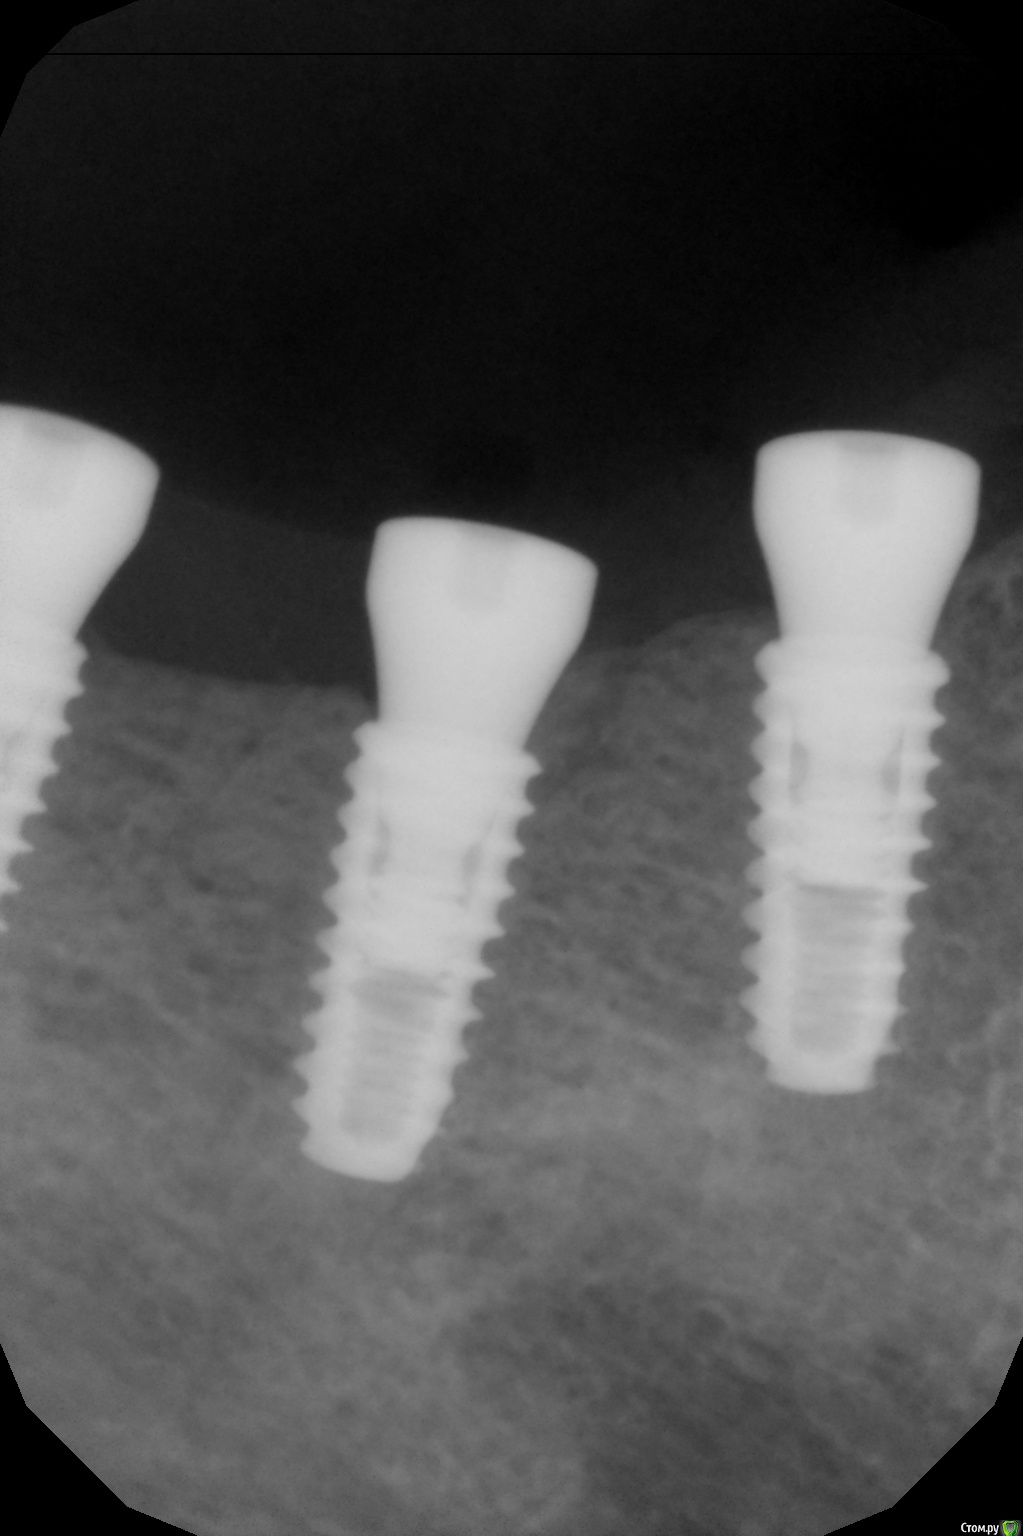

kamranchick Опубликовано 8 февраля, 2017 Автор Поделиться Опубликовано 8 февраля, 2017 А что и какой размер ставили?Послабляющий распил не делали?я тут не делал распилы, тут нет расщепления3,5-8,5 Ссылка на комментарий

kamranchick Опубликовано 8 февраля, 2017 Автор Поделиться Опубликовано 8 февраля, 2017 Спасибо за публикацию.Какова ширина гребня?5мм сверху в области кристального модуля имплантата дальше около 7мм) Ссылка на комментарий